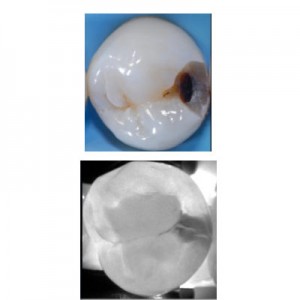

Nello scorso mese di Febbraio si è svolto presso la Sede KaVo di Milano il primo Meeting Internazionale "KaVo DIAGNOcam". Questo importante evento, che ha visto la presenza di 25 utilizzatori...